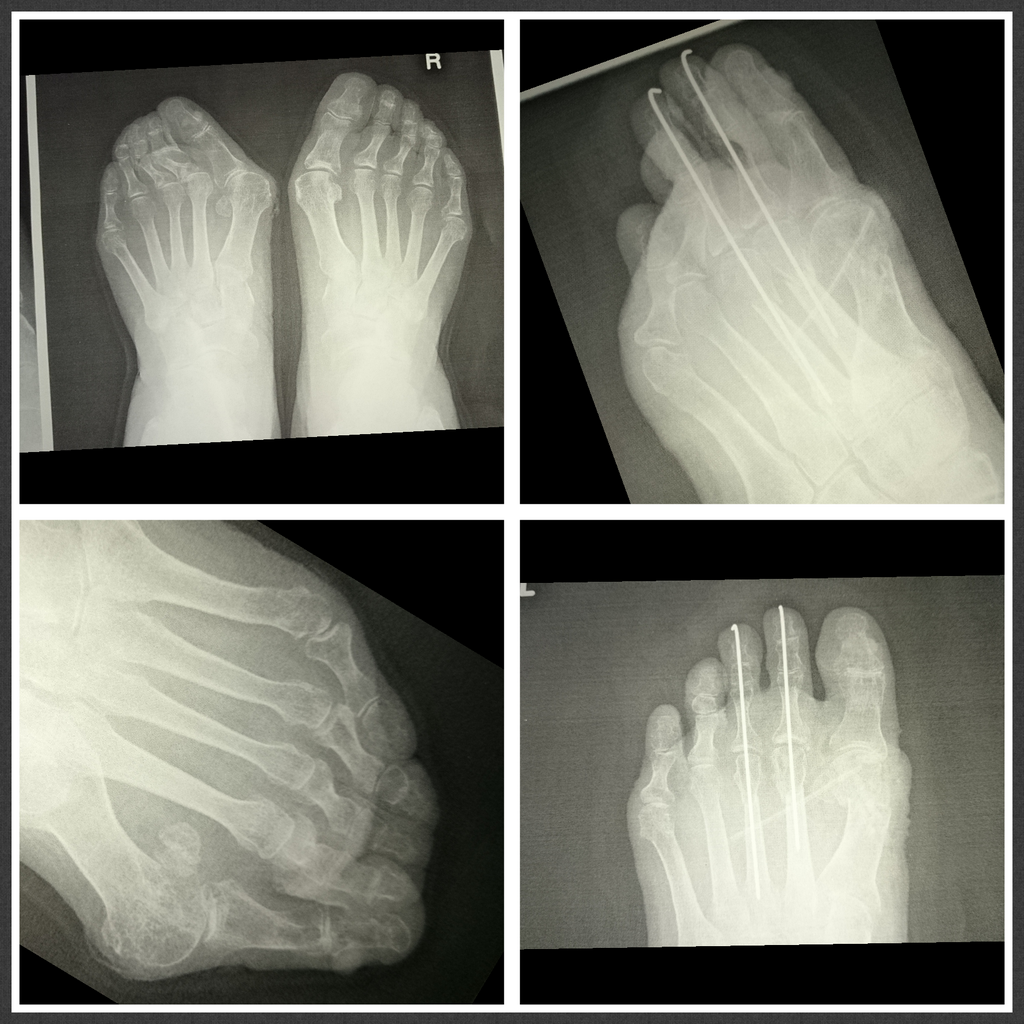

ご要望、足の痛み、靴の悩み、外反母趾、リウマチなどの